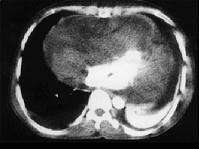

问题 35岁男性患者,一个月前开始间歇性发热,咳嗽、咳痰,足部肿胀,伴颈静脉怒张,行X线、CT检查如图所示,请选择正确的答案 ( )

选项 A、考虑原发性心包间皮瘤 B、考虑为心包炎 C、CT示示心包内见软组织肿块影 D、CT示心包弥漫性增厚,未见钙化影 E、X线示心影增大

答案 ACDE